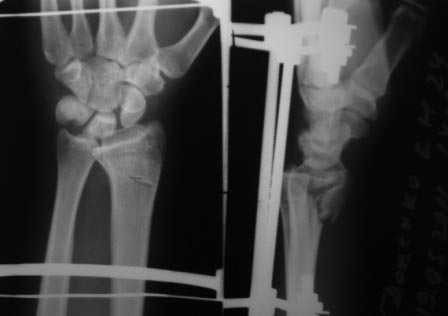

Нет не в вывихе, т. К. Из-за спицы проведенной через обе кости предплечья, то ротационные движения и подвижность локтевой кости резко ограничены, это может в некоторых проекциях расцениваться как подвывих, если найду покажу финальный снимок, там все рентгенологические показатели восстановлены.